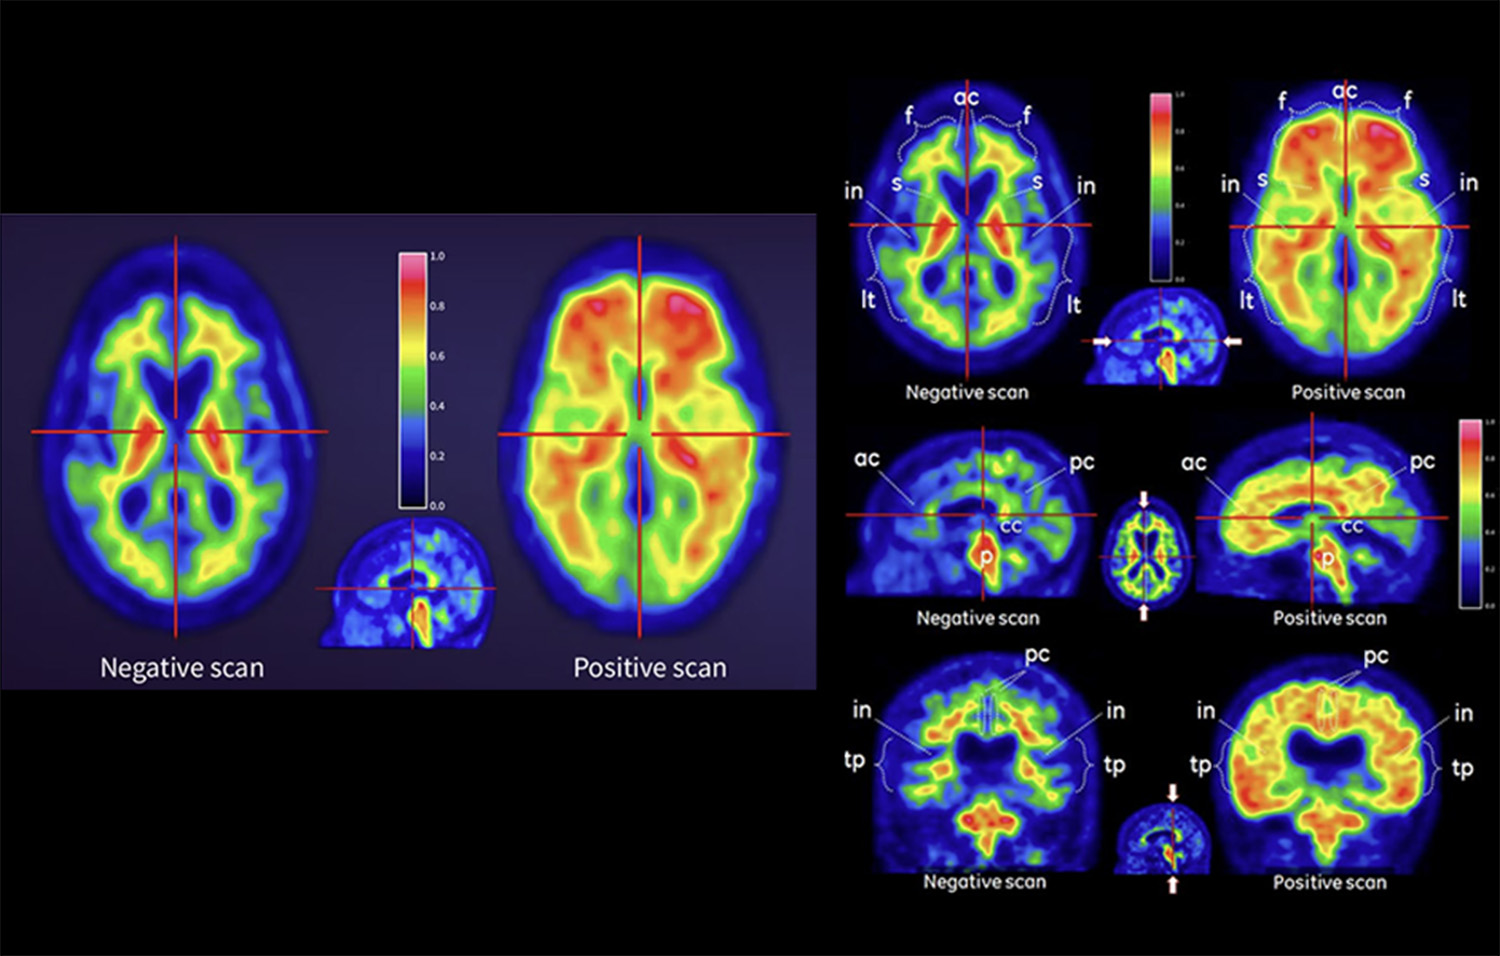

03. 18F‑Flutemetamol (FMM)

A radioactive diagnostic agent indicated for PET imaging of the brain to estimate β-amyloid neuritic plaque density in adult patients with cognitive impairment.